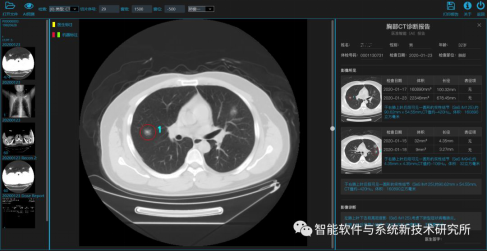

7. 基于深度学习的新冠肺炎早期检测筛查模型系统

所研发的系统针对新型冠状病毒病人存在的肺部病灶特征,可以做到新冠肺部病灶征象的快速早期检测筛查,是一个具有高效、高精度、强泛化能力的新冠肺炎早期智能检测分型模型及共享平台。通过对实际门诊数据排查测试,该模型可以减轻医护人员近80%的工作量,新冠肺炎患者的检测召回率超过95%。